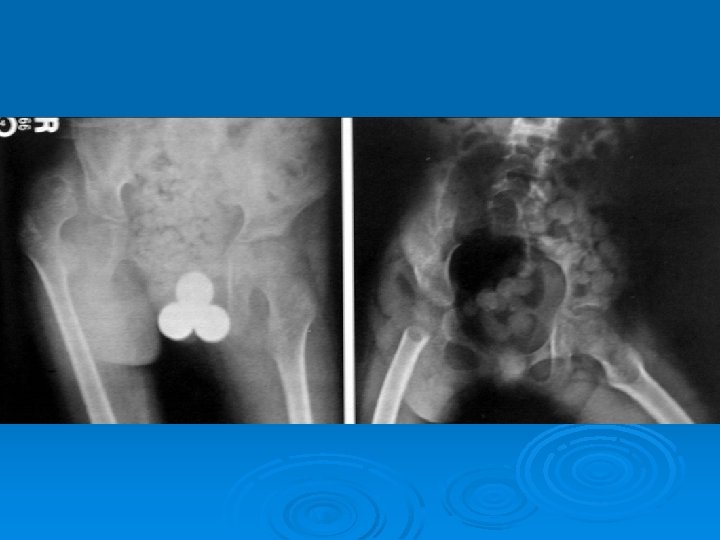

Deformities Lower limb : Ø Hip adduction/flexion/internal rotation Ø Knee flexion Ø Feet equinus / varus or valgus Ø Gait scissoring Spine : kyphoscoliosis

The two most important x-rays during follow up